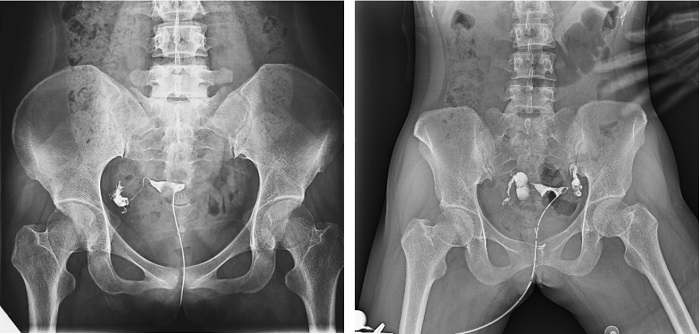

子宮輸卵管造影檢查損傷小,準確率高,是婦科檢查的常用方法。利用動態(tài)DRF進行子宮輸卵管造影檢查,大大超越了過去的檢查技術,更加精準高效。動態(tài)DRF矩形采集面積大,一次曝光即可顯示整個盆腔,大幅減少觀察時間,可控的瞬時照射避免受檢者吸收過多X線,對育齡期女性檢查尤為重要。可在造影劑流動的過程中完成拍片,抓拍到關鍵圖像,幫助醫(yī)生更加清楚地了解到管腔的具體通暢情況及堵塞部位,提高診斷的精準性。

▲輸卵管造影

普利德動態(tài)平板DRF床體智能化程度更高,在進行子宮輸卵管造影檢查時,醫(yī)生可以通過調(diào)整床體起倒角度精準控制造影劑的流動方向和速度,并根據(jù)造影劑在輸卵管及盆腔里的顯影準確判斷輸卵管堵塞部位、程度及性質(zhì),極大提高了拍片效率和診斷的精準性。